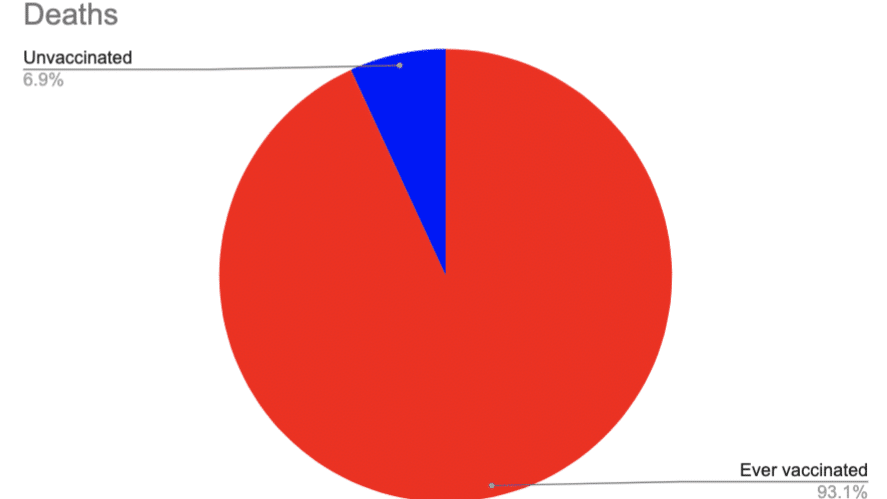

“Recently, the Centers for Disease Control and Prevention put forward some statistics regarding coronavirus vaccines’ capability to prevent death which have made people concerned. “According to the data shared by the CDC, coronavirus vaccines are capable of pr

Direct from the UK Government (Graph above is total 1 April 2021 and 31 May 2023) https://www.ons.gov.uk/peoplepopulationandcommunity/birthsdeathsandmarriages/deaths/datasets/deathsbyvaccinationstatusengland Download the spreadsheet and check (Table 5) https:/